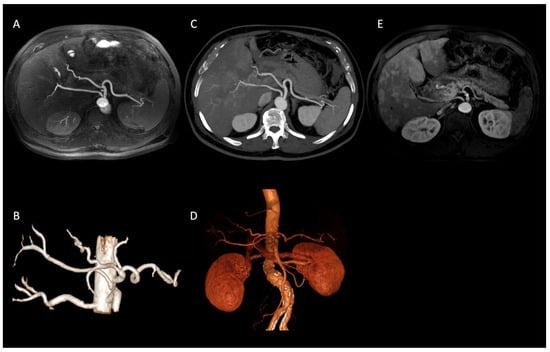

In our population, we observed several visceral vessels variants. Type I turned out to be the most common pattern, being present in 47 patients (67%), according to the incidence reported in literature (55% to 81%) [12,22]. The other variants were distributed as follows: Type V in 10 patients (14%); Type VI in 6 patients (9%); Type III in 2 patients (3%); Type IX in 2 patients (3%); Type XI in 2 patients (3%) (Figure 2); Type VII in 1 patient (1%).

Figure 2. Axial IFIR-MRA (A) and CTA (B) MIP reconstructions properly showing the direct origin of the right hepatic artery from the aorta (Type XI according to Michels’ classification system) and the remaining main celiac trunk branches up to the proximal bifurcations (spleen and hepatic hilum). On MRA (C) MIP reconstruction image quality and resolution are lower, not allowing the proper assessment of proximal bifurcations. IFIR-MRA (D) and CTA (E) 3D reconstructions, showing a comparable diagnostic performance.